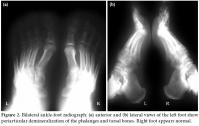

Routine laboratory investigations disclosed no abnormalities. Electromyography disclosed involvement of the left S1 root (gastrocnemius muscle had 2+ waves with mild decreased motor unit numbers) and corresponding paraspinal muscles suggestive of preganglionic damage; sensory and motor conduction was normal. Foot radiographs showed a pattern of osteopenia consistent with left CRPS (Figure 2). Technetium-99m methylene diphosphonate (Tc-99m MDP) three-phase bone scintigraphy (TPBS) confirmed the clinical diagnosis of bilateral CRPS by detecting the mild or intense increased activity uptake in a dynamic, early blood pool, especially in delayed static images (Figure 3).

The characteristic appearance of the roentgenogram in CRPS is that of extensive mottled demineralization. The TPBS is valuable, particularly in mild or early cases of CRPS where roentgenograms of the extremities may be negative.[3] In our case, direct radiography showed the characteristic appearance only on the left foot, but the right foot appeared normal. In the early period when the right foot appeared normal on radiographs, the bilateral occurrence of CRPS was detected by the TPBS showing the mild or intense increased activity uptake in a dynamic, early blood pool, especially in delayed static images.[3,14] While symptoms of CRPS associated with LDH in the literature either begin or subside with a disc operation,[3-7,9] conservative measures relieved both the LDH and the CRPS in our case. The symptoms in our case resolved with medical therapy consisting of NSAIDs, calcitonin and gabapentin in addition to a rehabilitation program including exercise and physical therapy.